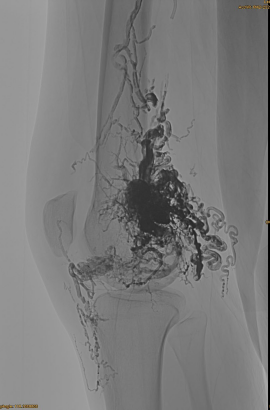

Grunnupplýsingar sjúklings: Kona, 36 ár; AVM mjaðmagrind, mjöðm, hné, vinstri osg, margfeldi fyrir - embolatizations.

Upphafleg DSA:

Lokaniðurstaða:

Varla öll bláæðarútstreymi:

Seint áfangi, annar embo nauðsynlegur, en miklu betri: